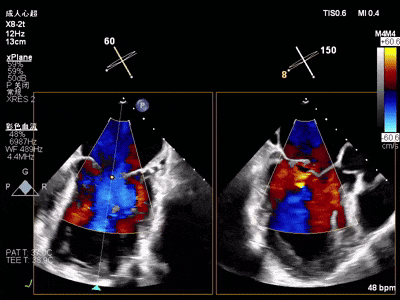

术前术后对比图

术前

术后

术后,出院检查报告显示夹子位置固定,无移位,二尖瓣轻度反流,左室大小和LVEF值正常范围,左室壁运动分析未见明显异常。

术前术后对比图:

术后,出院检查报告显示夹子位置固定,无移位,二尖瓣轻度反流,左室大小和LVEF值正常范围,左室壁运动分析未见明显异常。术后两个月随访检查,状态稳定,夹子位置固定,二尖瓣轻度反流,左室大小和LVEF值正常范围,左室壁运动分析未见明显异常(左室壁运动记分指数1分)。

术后,出院检查报告显示:夹子位置固定,二尖瓣轻度反流,左室稍大,LVEF值正常范围,左室壁运动分析未见明显异常(左室壁运动记分指数1分)

术后,出院检查报告显示夹子位置固定,二尖瓣、三尖瓣及主动脉轻微反流,左房增大,左室内径正常上限,EF值正常下限(WMSI 1分)。